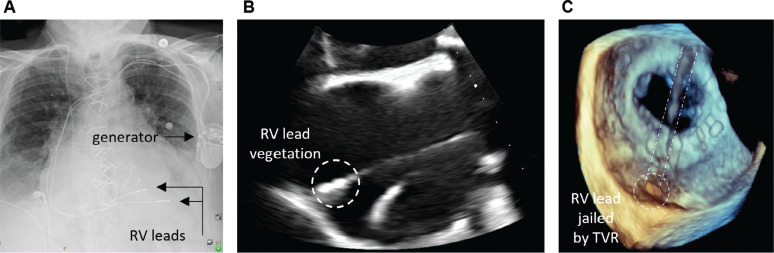

An 85-year-old woman presented with Corynebacterium bacteremia complicated by infective endocarditis with vegetations on the prosthetic mitral valve and right ventricular (RV) lead. The patient had a single-chamber permanent pacemaker with two RV leads, one of which was previously trapped or "jailed" after a bioprosthetic tricuspid valve replacement. Complete transvenous lead extraction including the chronically retained jailed RV lead was achieved via laser extraction assisted by concomitant traction from a superior left subclavian and inferior right femoral venous approach.